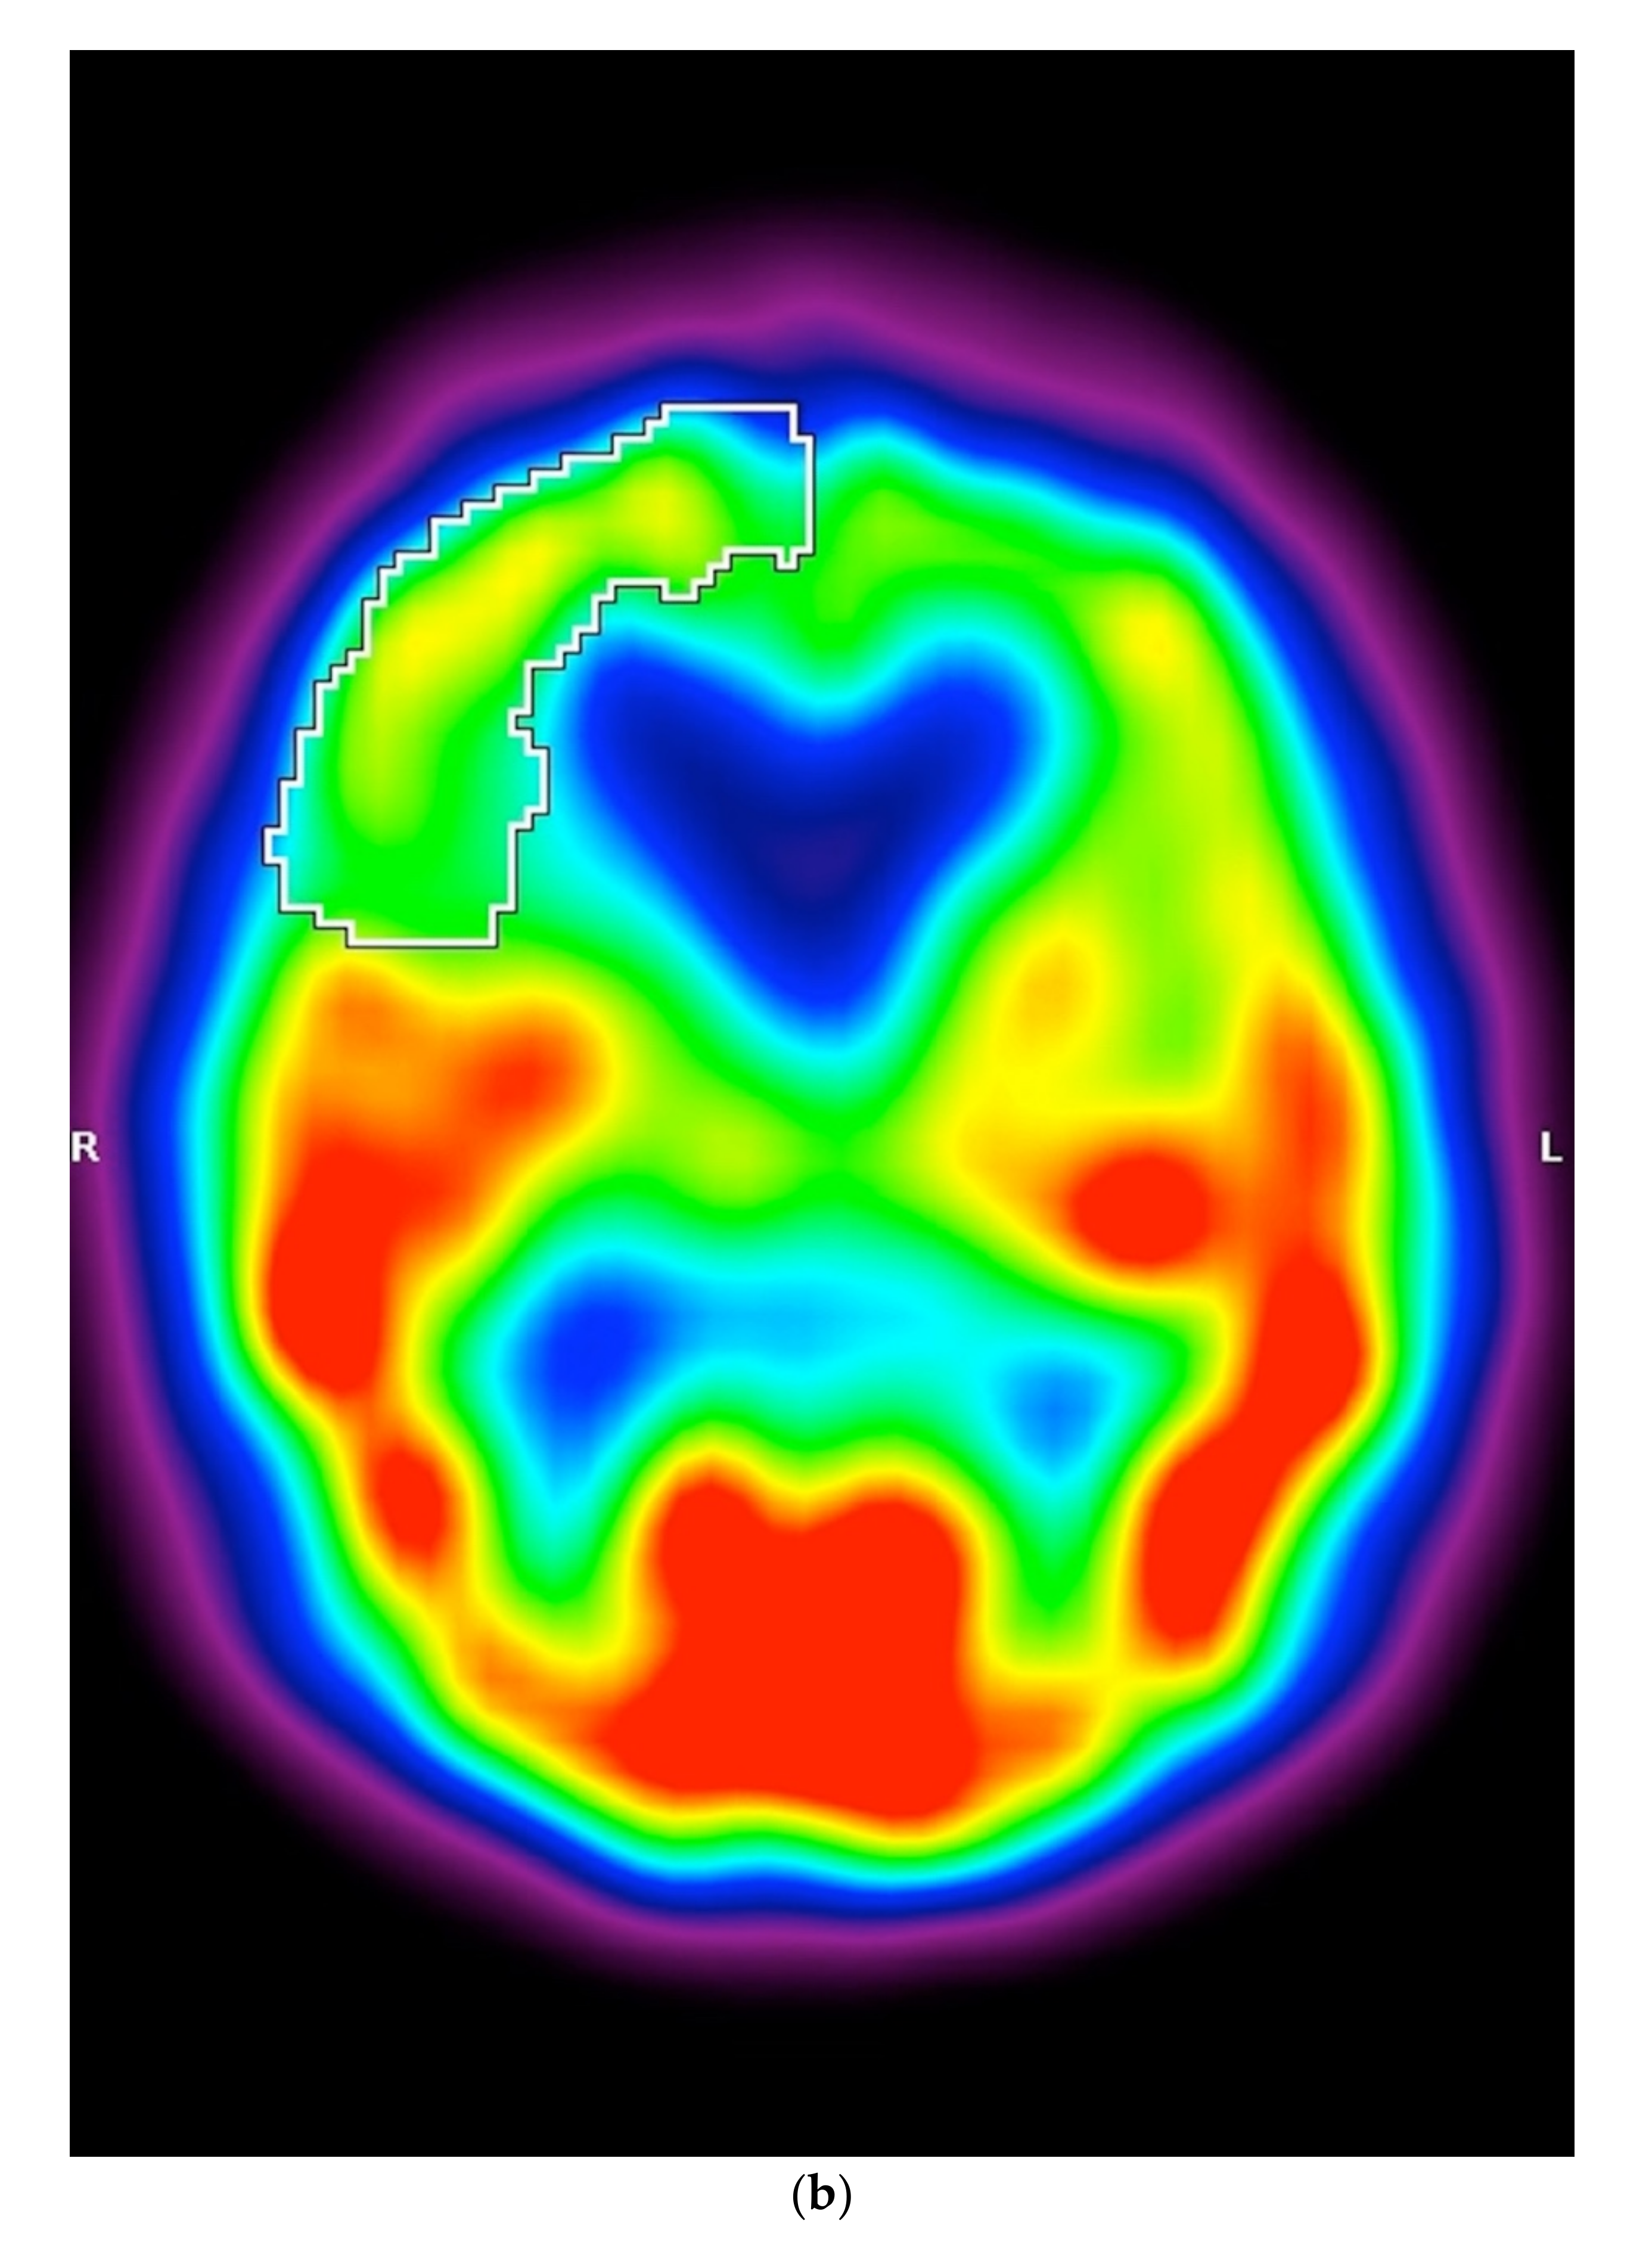

3.2. SPECT

5.1.3. SPECT